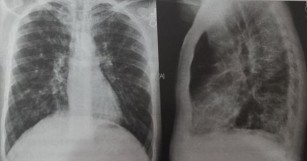

Fibroza pulmonara defineste cicatrizarea tesuturilor pulmonare. Plućnu fibrozu može uzrokovati mnogo bolesti posebno one koje uključuju nenormalnosti imunološkog sustava reumatoidni artritis sklerodermija sistemski lupus eritematodes. Jde o autozomální recesivní vrozené onemocnění způsobené mutací genu produkujícího protein cftr anglicky cystic fibrosis transmembrane conductance regulator. Fibroza pulmonara defineste cicatrizarea tesuturilor pulmonare.

Fibroza este termenul medical care descrie cicatricile. Jedná se o gen uložený na dlouhém raménku 7. Aceasta afectiune poate fi provocata de mai multe afectiuni inclusiv procese inflamatorii cronice sarcoidoza granulomatoza wegener infectii interactiunea cu diversi agenti de mediu azbest siliciu anumite gaze expunerea la radiatii ionizante radioterapia de. Fibroza je formiranje viška vlaknastog vezivnog tkiva u organu ili tkivu u reparativnom ili reaktivnom procesu.

Fibroza pluća uzroci. One such tumor is known as a fibroma. Fibróza je stav zmnožení vaziva typu pojivové tkáně jakožto důsledku hojivého procesu po zánětu zranění či reparativní reakce na různé typy podnětů včetně příčin nejasné etiologie. Fibrotickým procesem se u parenchymatózních orgánů zvyšuje poměr vaziva na úkor funkční tkáně dochází ke snížení fyziologické funkčnosti a jejich ztuhnutí.